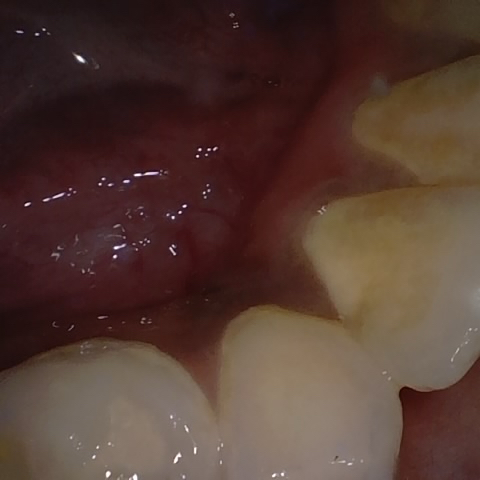

Annotated as "Good"